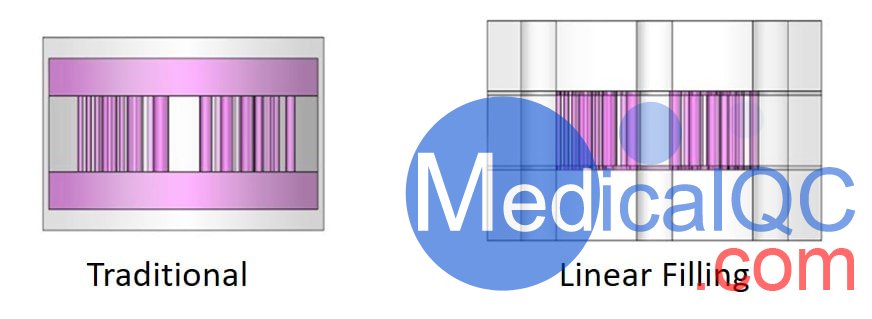

這些體模還具有我們獲得專利的線性填充技術(shù),該技術(shù)可大大減少填充體模所需的體積,確保均勻填充并減少對體模處理者的劑量。所有這些都通過減少噪聲來改善圖像質(zhì)量。

線性填充是通過分段結(jié)構(gòu)實(shí)現(xiàn)的,該結(jié)構(gòu)創(chuàng)建了一條穿過所需體模的長蛇形通道。該鏈條既包括具有所需孔型的熱棒,也包括連接相鄰熱棒的連接通道。通過單個(gè)入口和出口,可以使用Luer Lock注射器輕松地將流體驅(qū)入體模。這樣就無需手動填充容易因表面張力而產(chǎn)生氣泡的小孔。

此外,用于創(chuàng)建復(fù)雜的孔圖案典型技術(shù)包括孔圖案的在放射性池浸沒。該技術(shù)消除了最終的輻射池,通過消除背景噪聲的主要來源,大大減少了模體的內(nèi)部體積并提高了圖像質(zhì)量。